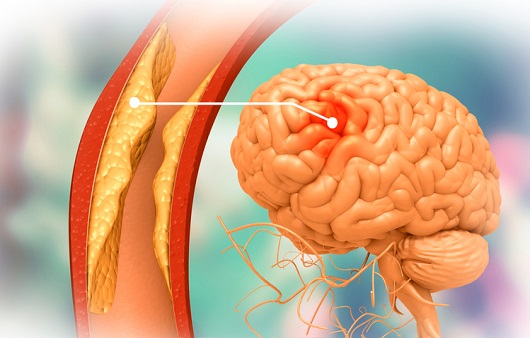

먼저 뇌경색이 무엇인지에 대해 쉽게 설명드리겠습니다. 뇌경색은 뇌로 가는 혈류가 차단되어 발생하는 질병으로, 일반적으로 뇌졸중이라고도 알려져 있습니다. 뇌혈관이 좁아지거나 막히면서 뇌가 필요한 산소와 영양분을 공급받지 못하게 되고, 이로 인해 뇌세포가 손상됩니다. 이러한 손상은 즉각적인 신체 기능 저하를 초래할 수 있으며, 심각한 경우 생명에 지장을 줄 수 있습니다.